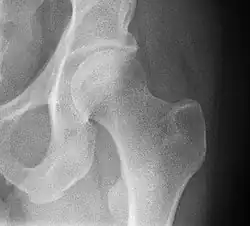

- Kleinere afwijkingen kunnen beter opgespoord worden met een röntgenfoto, soms samen met een contraststof. Het röntgenonderzoek kan pas plaatsvinden 5 tot 6 maanden na de geboorte, omdat het kraakbeen eerst tot bot moet worden omgevormd voordat de dysplasie op de foto kan worden gezien.

Er zijn nog andere beoordelingsmethoden voor het beoordelen van Röntgenfoto's zoals de heupkommeting naar Hilgenreiner (AC-meting, AC staat voor acetabulum), de heupkommeting naar Idelberger en Frank (ACM-meting), centrum-hoekmeting naar Wiberg (CE-meting, CE staat voor centre-edge), de heupkommeting naar Lequesne en de Sèze (VCA-meting) en de heupkomopeningsmeting naar Ullman en Sharp.